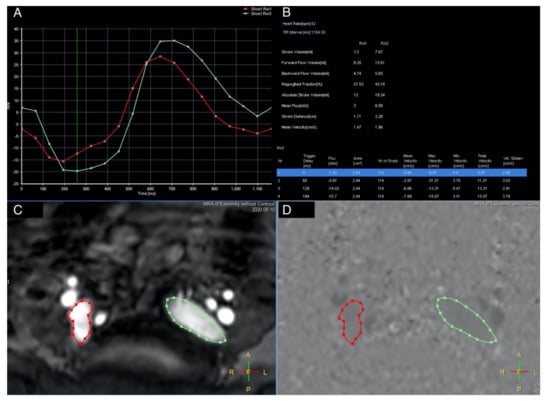

A quantitative analysis was performed by drawing the region of interest (ROI) on the vascular lumens (covering the whole lumen) at each set point by a specialized radiologist (CWC), including the external iliac veins, femoral veins, greater saphenous veins, and popliteal veins. Each ROI automatically generated eight variables, including the stroke volume (SV), forward flow volume (FFV), backward flow volume, regurgitant fraction, absolute stroke volume, mean flux (MF), stroke distance (SD), and mean velocity (MV) (Figure 3). In summary, we used TRANCE for morphological imaging and then used a phase contrast GRE technique to measure the blood flow at set points. Both of the external iliac veins, femoral veins, popliteal veins, and greater saphenous veins were analyzed.

Figure 3. QFlow scan in a TRANCE MRI consisting of the stroke volume, forward flow volume, backward flow volume, regurgitant fraction, absolute volume, mean flux, stroke distance, and mean velocity. (A) Two external iliac veins with the flow sequence by time. (B) QFlow parameters with different trigger delays. (C) Regions of interest of both the external iliac veins. (D) Image during data acquisition. (green circle: left external iliac vein, red circle: right external iliac vein).